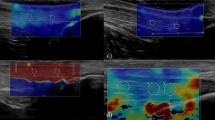

Two observers participated in this study and both of them used the same ultrasound system (LOGIQ E9; GE Medical Systems, Wisconsin, USA) with a 9-MHz linear probe. The first observer (HNS, 11 years experienced in musculoskeletal radiology) performed B-mode ultrasound and measured thickness of bilateral CETs (n = 60) of all volunteers at the level of the humeroradial joint and then used the SWE imaging to measure the stiffness values of all subjects in kPa consecutively (Figs. 1, 2). The second observer (EC, 10 years experienced in musculoskeletal radiology) performed only elastographic evaluation of all CETs just after the first examination had ended. The observers were blind to their results. All the volunteers were examined in the sitting position with 90° flexion of elbow and the thumbs up. The tip of the linear probe was covered with a generous amount of ultrasound gel and to avoid anisotropy, the probe was placed parallel to the longitudinal axis of the CET. The stiffness measurements were made by using 2-mm region of interest (ROI) at the level of the capitellar region. All ROIs included only the tendon structure. CET stiffness values were measured three times by both observers and the median of the consecutive three measurements was recorded. Consecutive measurements were made from approximately the same area of the tendon at the capitellar region on different elastography images.